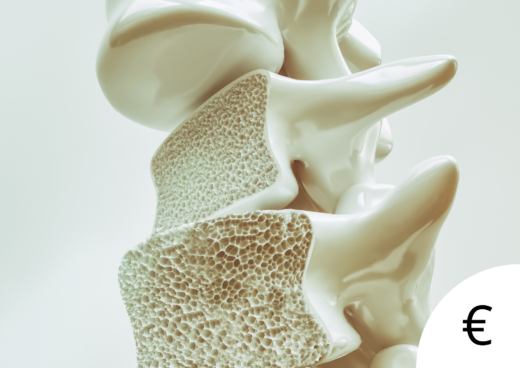

Luu on elav kude, mis laguneb ja mida ehitatakse üles jätkuvalt kogu inimese elu jooksul. Osteoporoos tekib siis, kui lagunemisprotsessid saavad ehitusprotsessidega võrreldes ülekaalu. Vastupidiselt levinud arvamusele ei ole niisuguse olukorra põhjuseks ainuüksi toiduga saadava kaltsiumi vähesus.